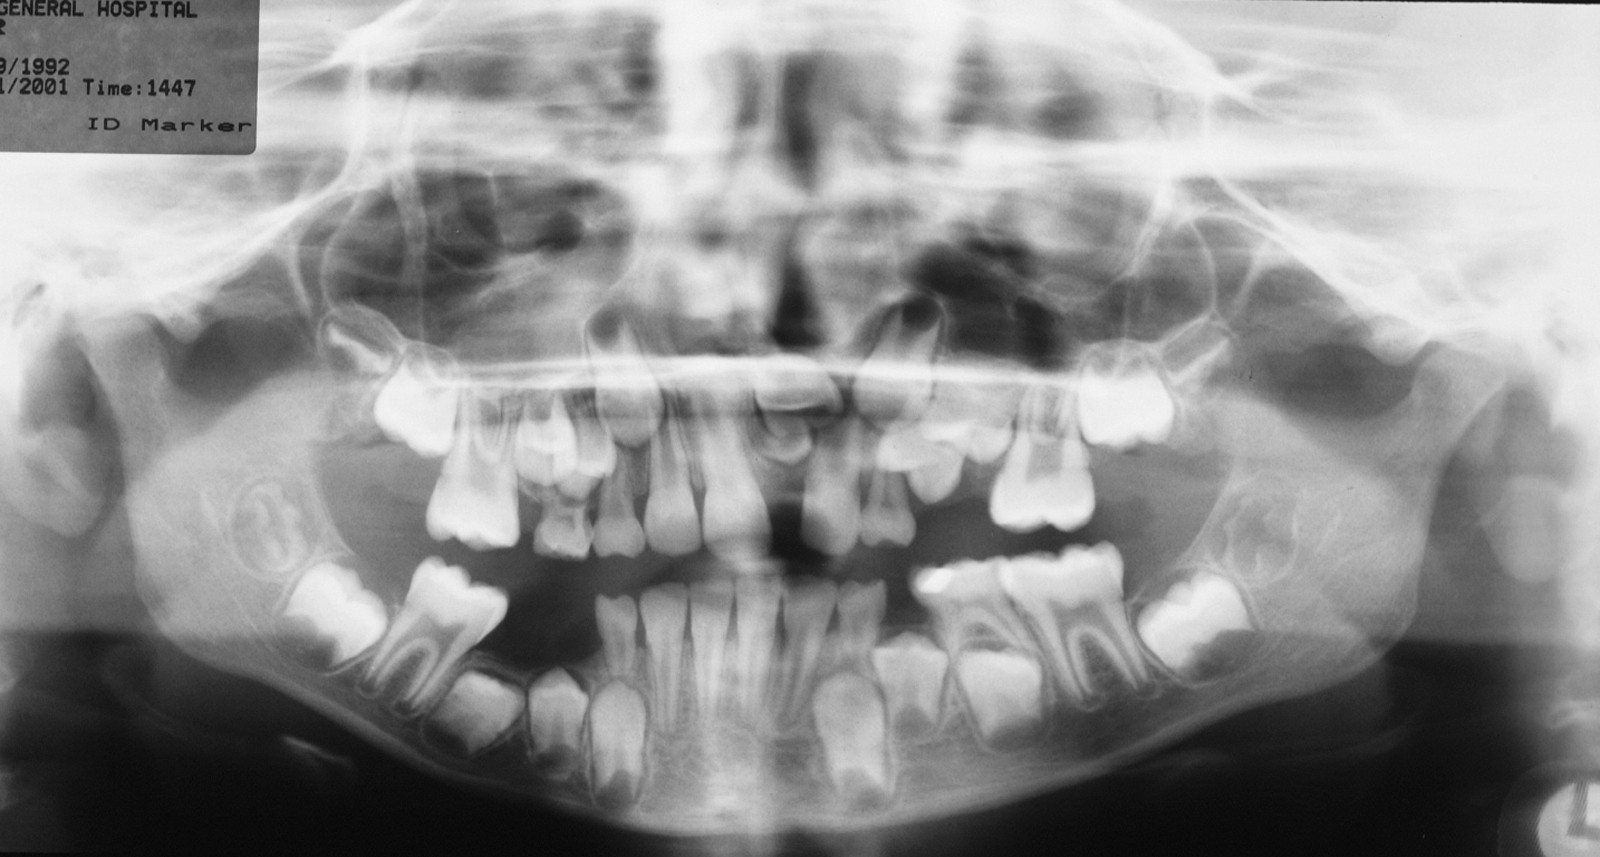

The root pattern (Figure 11) and relationship to the inferior alveolar nerve bundle, to the adjacent second molar, and to bone of the ascending ramus of the mandible can all create problems with simple elevation of third molars. Sectioning the tooth is the safest technique to overcome this. The tooth is decoronated by cutting through the amelo-cemental junction (about 80% through), then the crown is fractured off with an elevator. If the tooth is still resistant to elevation, the roots are separated by cutting through the bifurcation and elevating them individually (Figure 12).

Injury to the inferior alveolar nerve is less common but harder to manage. The nerve may be directly injured by the needle during the injection of local anaesthetic or may be crushed by the tooth root during elevation. Rarely the roots of the tooth may surround and encase the nerve so that elevation is unavoidable. Clues to this injury can be seen on the radiograph and when the tooth will not elevate easily (it actually feels as if it is attached by a rubber band).

Increasing availability of cone beam computed tomography scans (CBCT) can be useful in assessing lower third molars whose roots are in close proximity to the inferior alveolar nerve and helping to determine the risk of neurosensory disturbance. If such cases are identified, a decision may be made to remove the crown of the tooth only (coronectomy; see above).